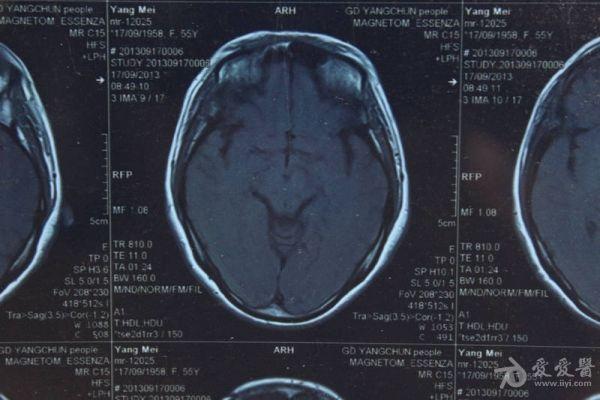

脑部占位病变CT,MRI图片,请帮忙诊断

最近感图样,无其它脑病病史

考虑脑膜瘤!!

磁共振没有平扫,增强矢状位没找到病灶。像脑膜瘤。

图片不是很清楚,应该是脑膜瘤!